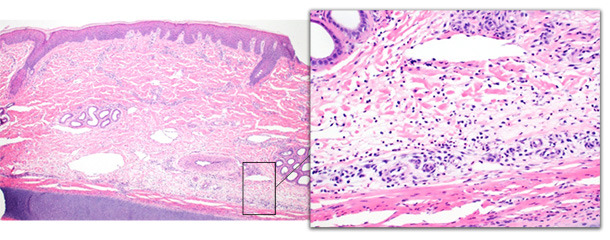

L’histopathologie de l’épiderme et du derme des porcs avec affection aigüe a montré une inflammation péri vasculaire de la couche profonde du derme avec des changements minimes de l’épiderme (figure 2). Les changements de l’épiderme comprenaient de l’acanthose et de l’hyperkératose orthokératosique. Sur un cas, les éosinophiles prédominaient, avec de la vascularite, de la thrombose et de la nécrose épidermique. Les changements sur les porcs atteints chroniquement comprenaient une ulcération, de l’acanthose irrégulière, une formation de tissus de granulation et une thrombose sur les couches profondes du derme (figure 3). Les changements chroniques sont semblables à ceux décrits précédemment (Jensen 2009, Richardson, Morter et al. 1984)

Figure 2 – Biopsie de la pointe de l’oreille d’un porc avec une affection aigüe. Le derme profond est distendu par un œdème et il y a un nombre modéré de neutrophiles avec des changements épidermiques minimes.